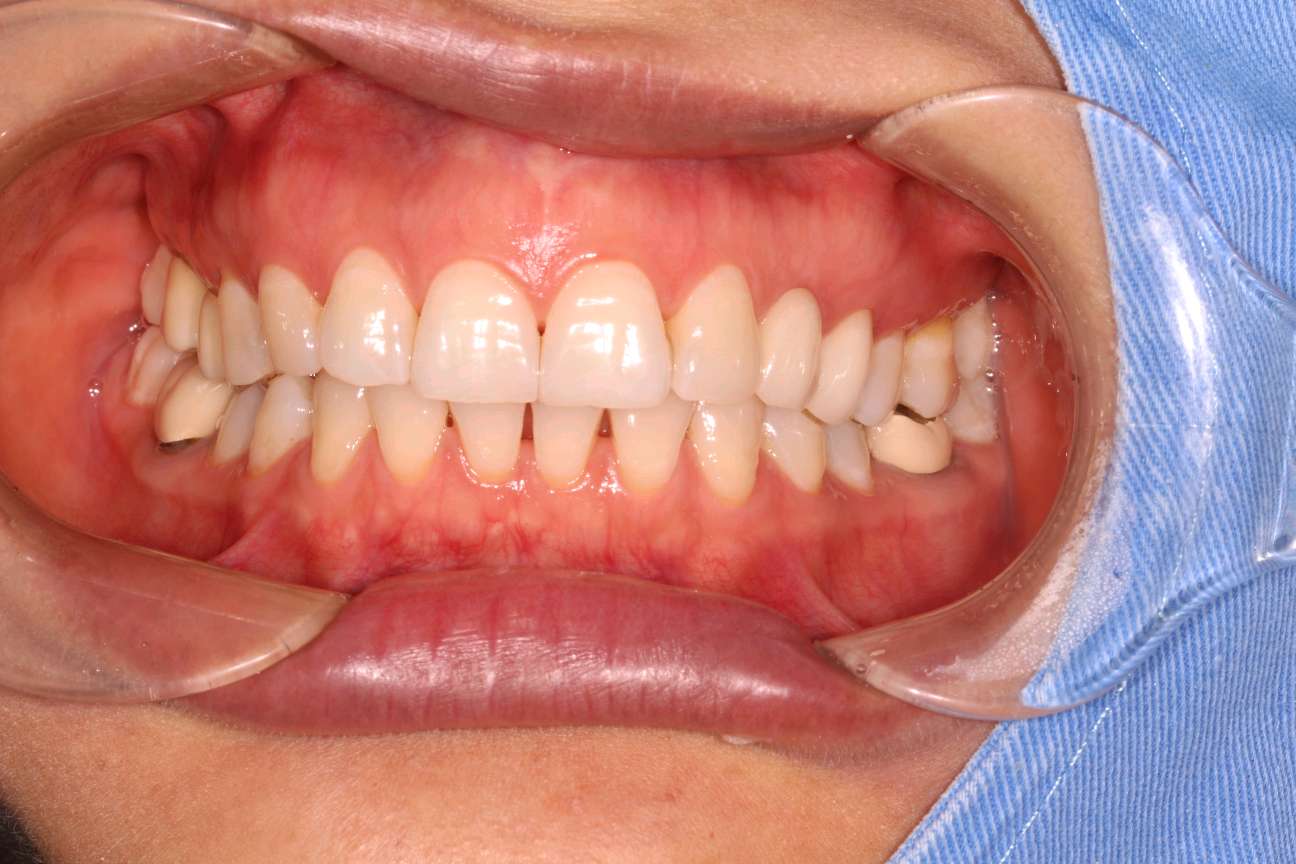

术后

修复效果:45 嵌体 、46牙 全瓷牙冠 修复 通透度极佳,色泽与患者真牙高度贴近,无异物感,患者非常满意。交代注意事项,常规医嘱。按时复诊,不适随诊。